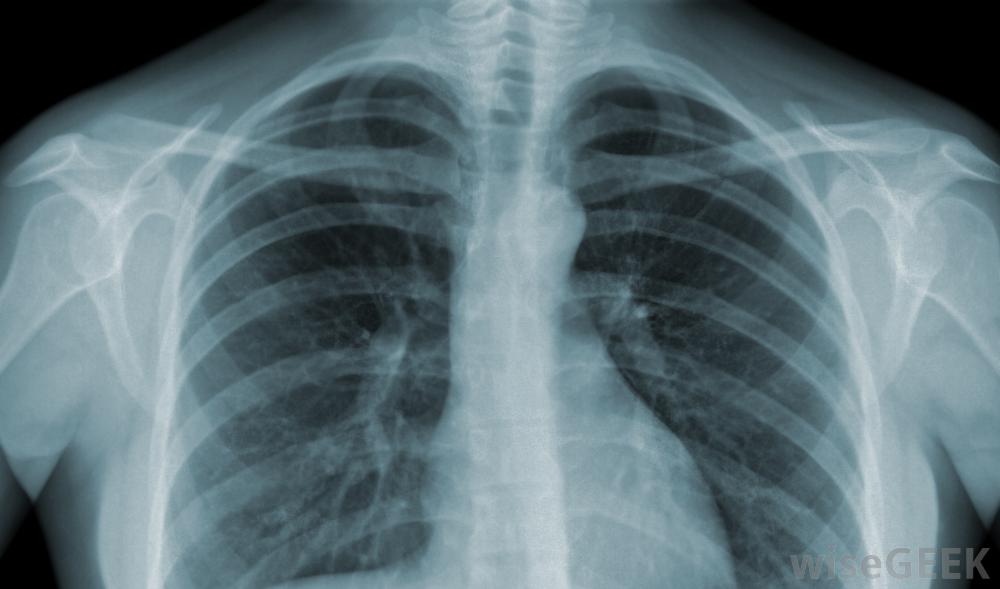

鎖骨遠端骨溶解癥,又稱舉重肩關節,是一種影響肩鎖關節的肩關節損傷。它通常與高應力作用于鎖骨或鎖骨的接觸性運動有關。但確切原因尚不清楚。癥狀可能緩慢出現,包括隱痛在AC關節上,活動性降低,肩部僵硬和腫脹,強度降低。持續活動可使癥狀惡化。肩關節活動性降低、僵硬和腫脹是鎖骨遠端骨溶解。骨溶解是指骨中礦物質(如鈣)的流失,導致骨頭軟化或溶解。在鎖骨遠端骨溶解中,末端或遠端,鎖骨開始緩慢分解和溶解。這可能是由AC關節的單一損傷、較小的重復性損傷、AC關節上的重復應力(如舉重)或可能影響骨結構礦化的既往疾病(如類風濕性關節炎)引起的鎖骨是連接肩膀和上半身的一塊水平骨,大多數人都能看到鎖骨骨結構的改變會隨著時間的推移而發生,但通常可以通過x光片和病史來診斷治療取決于骨丟失的程度。在大多數情況下,避免癥狀性活動或改變活動,加上消炎藥和冰塊,可以使鎖骨再礦化。這個過程可能需要兩年時間才能完全消除。如果恢復以前的活動,癥狀通常會復發鎖骨,也稱為鎖骨,連接肩部和胸骨骨不會再礦化,或者患者不能或不愿限制其活動。鎖骨遠端骨溶解最常見的手術形式是鎖骨遠端切除術,或關節鏡下鎖骨遠端切除術,切除受影響的部分骨。術后愈合時間不同,但范圍有限在手術后的一到兩周內,人的骨骼,包括紅色的鎖骨這種情況在某些情況下是可以預防的。專家建議一旦AC關節疼痛出現就停止所有加劇的活動。對于那些進行接觸性運動的人,建議使用額外的填充物。舉重運動員可以通過更窄的握力來避免受傷,避免肘部鎖定或過度伸展鎖骨隨時間的變化可通過X光片進行診斷。第一次記錄的鎖骨遠端骨溶解損傷是在1936年。在本例中,一名空氣錘操作員表現為肩部酸痛,沒有明顯的外傷。隨著意識和競技運動的普及,這些損傷的發生率增加。休息和冰敷是兩種治療方法將用于鎖骨遠端骨溶解。肩鎖關節損傷的患者可以從物理治療中受益大多數肩鎖關節損傷發生在運動或運動中導致骨溶解。